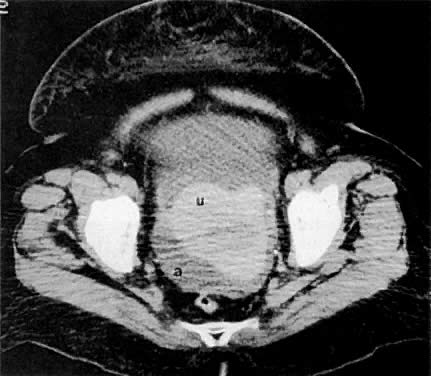

The presence of hydrometras should raise the suspicion of cervical or endometrial carcinoma. It is best demonstrated by ultrasound (see Fig. 6A), but can be seen by both MRI (Fig. 7) and CT (Fig. 8).11,12 This finding, however, is nonspecific because it can also be seen in benign cervical strictures caused by either previous cervical inflammation (Fig. 9) or pelvic irradiation (Fig. 10).

Fig. 8. Axial CT scan of the pelvis in a 55-year-old woman with stage IB cervical carcinoma causing obstruction of the uterus ( u ). ( b, bladder; arrows, uterus; r, rectum.)